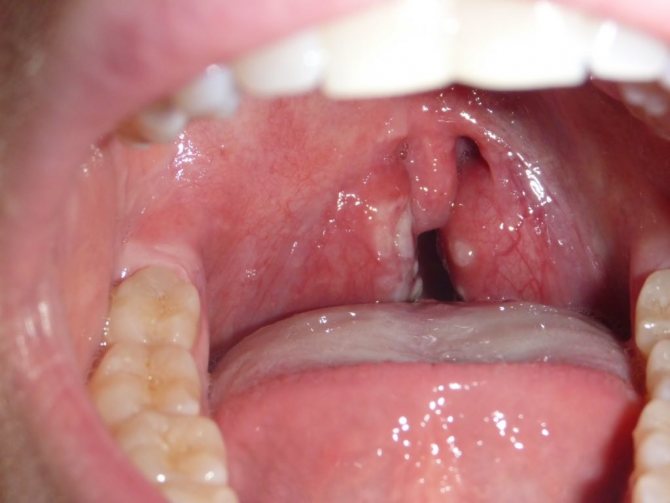

- Гнойный процесс в небных миндалинах. Наблюдается повышение температуры, болевой дискомфорт при глотании слюны и пищи, пересыхание полости рта.

При осмотре у таких людей виден серовато-белый налет, напоминающий рыхлую пленку, под которой находятся пузырьки с мутноватым экссудатом.

При запущенных формах стоматита, когда грибковый возбудитель попадает в лимфоузлы за ухом, на затылке или под челюстью и появляются признаки лимфаденита, у больных во рту обнаруживают афтозные язвенные высыпания – язвочки появляются после разрыва пузырьков.